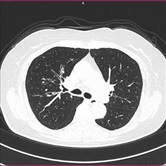

胸部CT画像 腹部CT画像